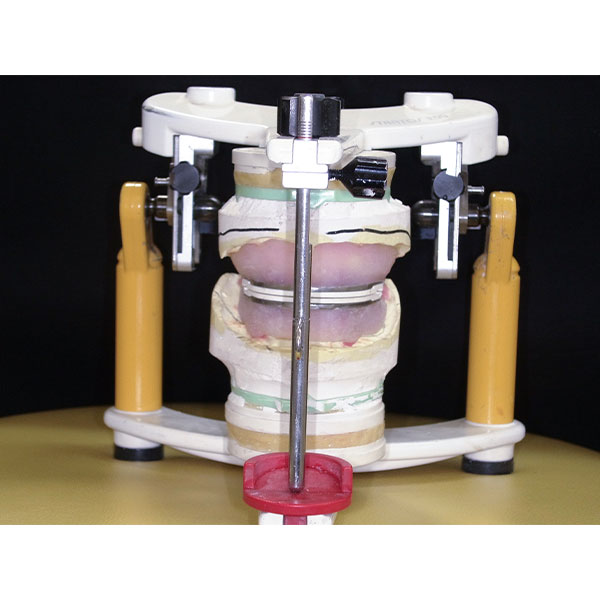

Après la mise en moufle et l'ébouillantage, les dents ont été repositionnées, conditionnées et des caractérisations blanchâtres, pourpres, orange clair, bleues et roses ont d'abord été réalisées au niveau du le bouclier labial. La base a ensuite été incrustée de résines pour prothèses de couleurs orange-rouge, rouge foncé, rouge clair, rose et rose foncé, et tous les polymères à chaud ont été pressés en une seule fois. Après le stockage sous pression, les prothèses finies ont été démouflées, finies et polies. La stratification anatomique tridimensionnelle de VITAPAN EXCELL en masse d'émail, de collet et de dentine avait un aspect absolument naturel dans l'anatomie muco-gingivale reproduite de la base prothétique. Le patient a pu s'habituer rapidement à sa nouvelle prothèse, notamment grâce à l'effet esthétique réussi. Après une courte phase d'adaptation et des corrections minimes dans l'environnement biodynamique, il s'est très bien débrouillé avec sa première restauration prothétique amovible complète et en était pleinement satisfait.